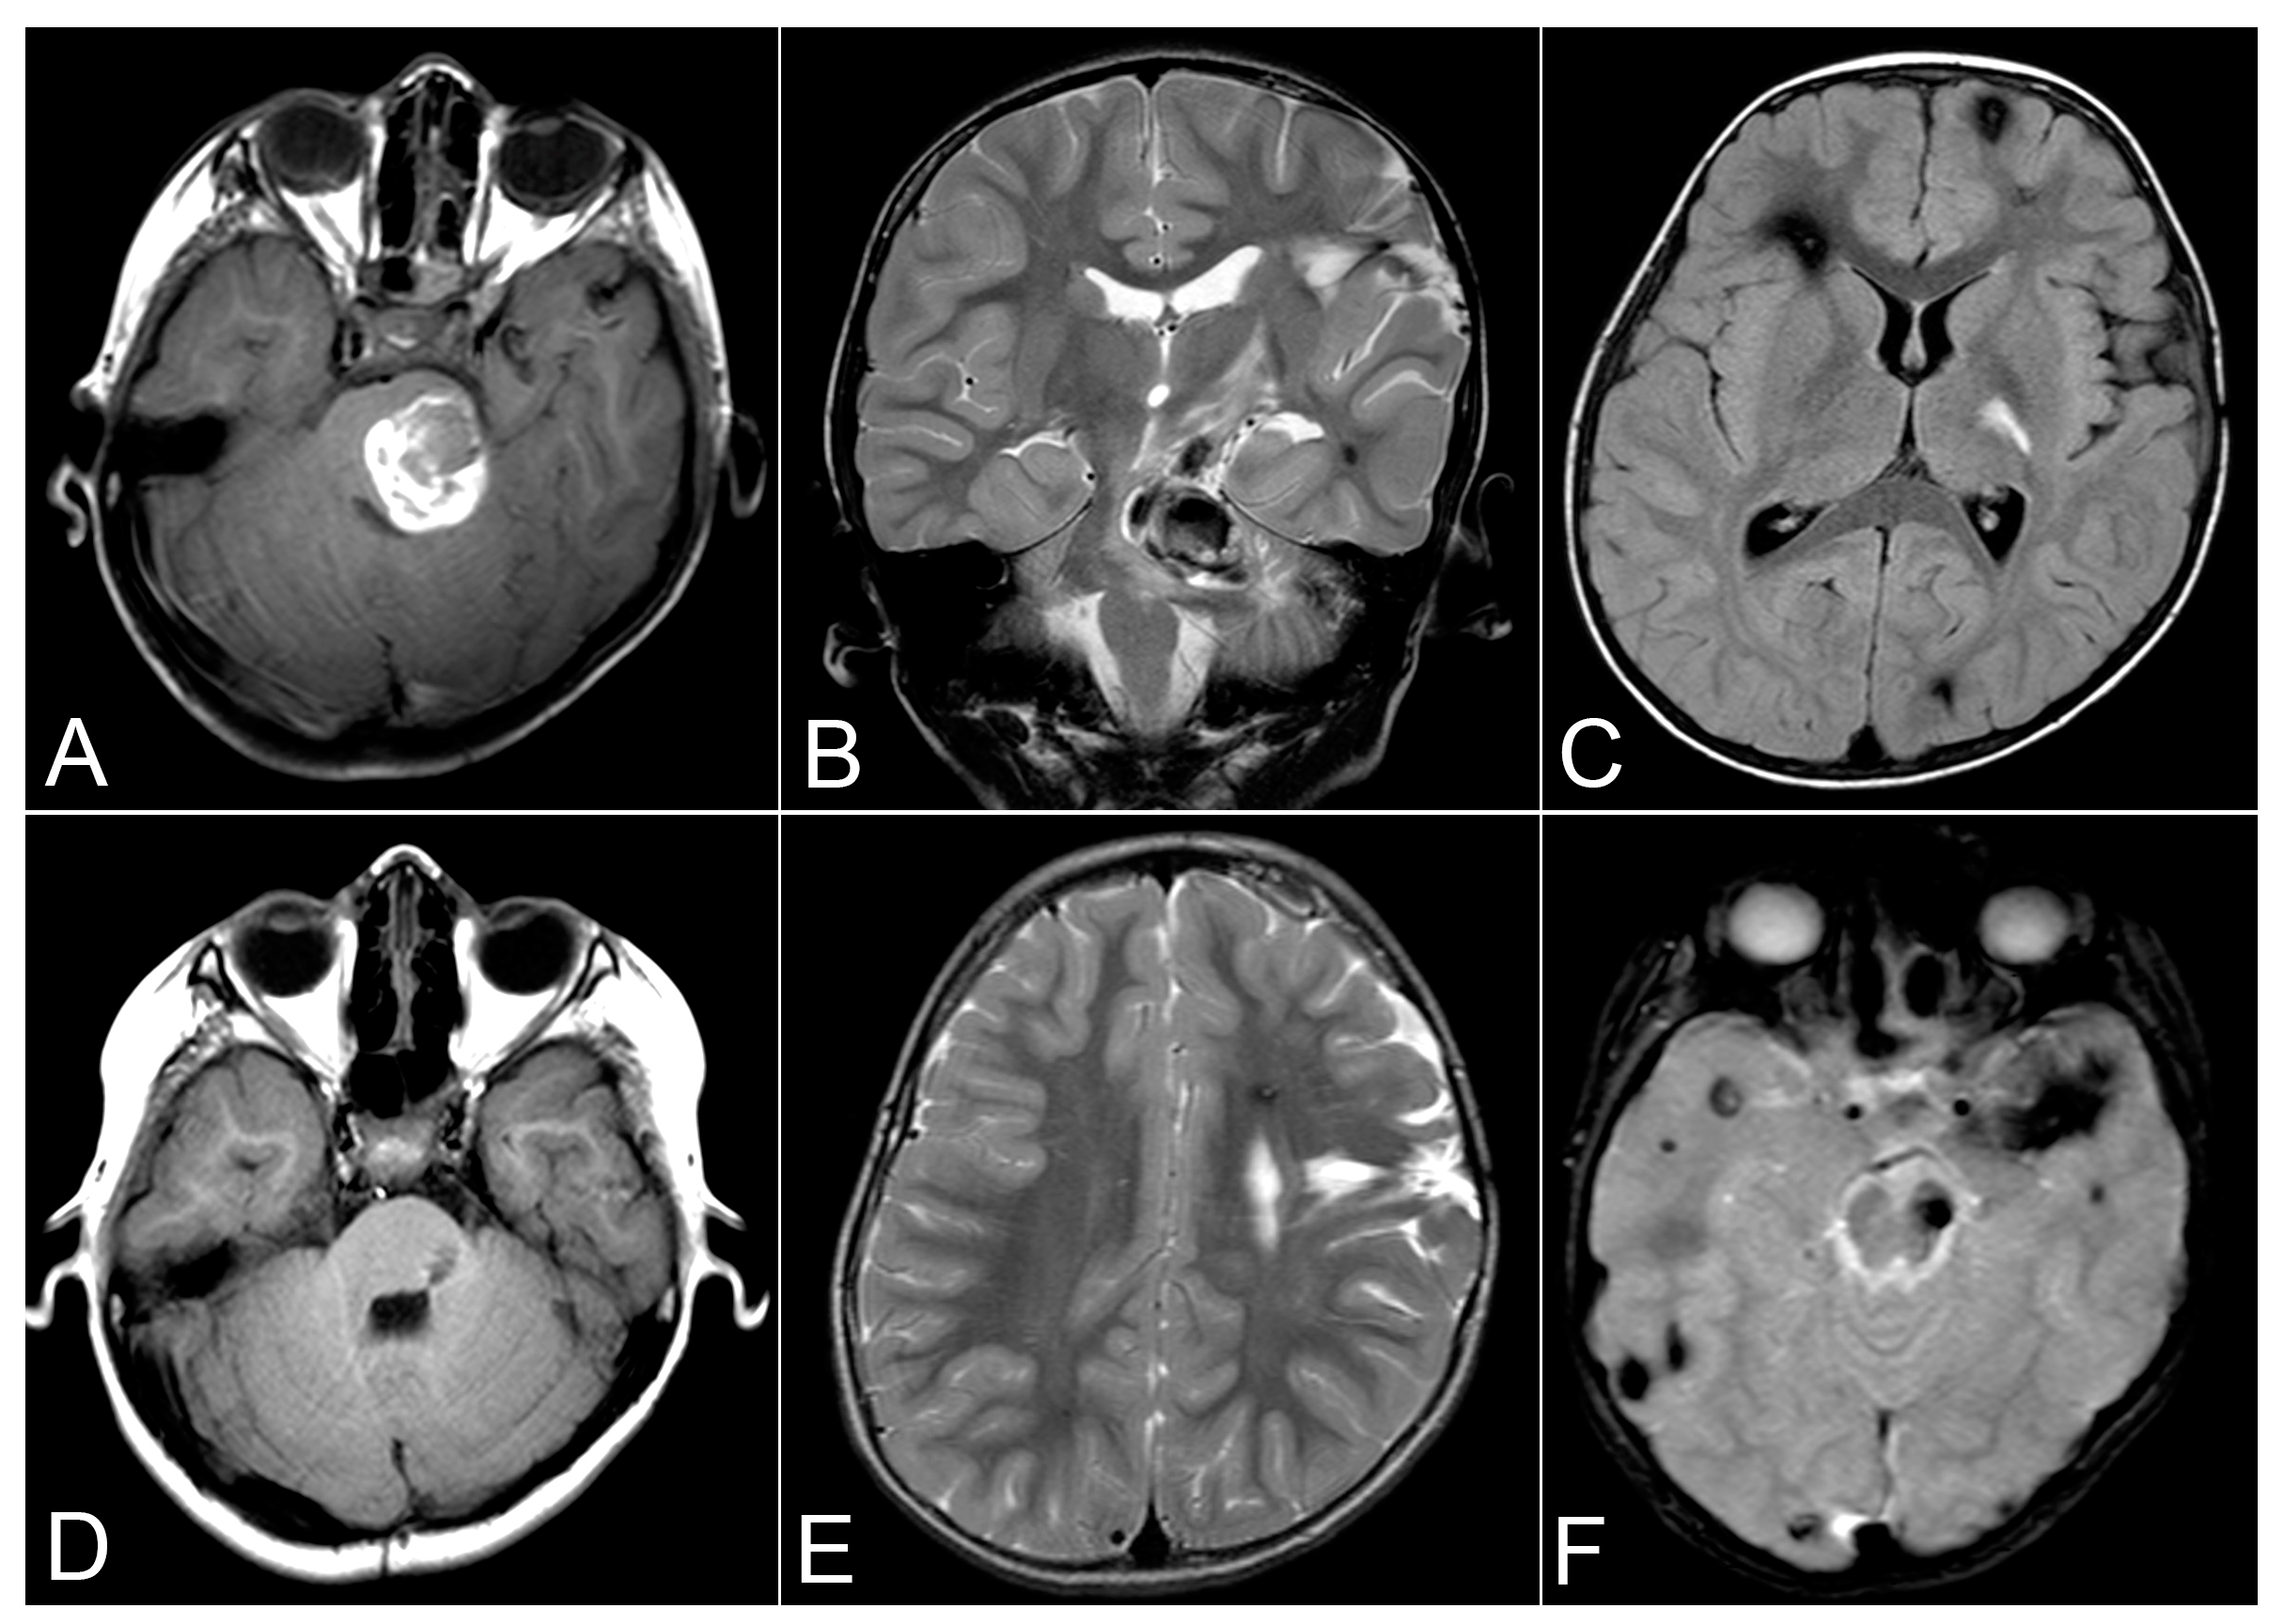

| 1st admission | 2 November 2010 | MRI (Axial T1, SWAN) | Multiple CCMs, large hematoma in the left frontal lobe, small CCM in the left frontal lobe |

| 1st admission | 2 November 2010 | MRI (Axial T2) | CCM in the left temporal lobe |

| 1st admission | 2 November 2010 | MRI (Axial SWAN) | CCM in the right occipital lobe |

| 2nd admission | 18 August 2015 | MRI (Axial T1, Coronal T2) | Large hematoma in the left pons, multiple small lesions in both hemispheres, gliosis in the left frontal lobe |

| 2nd admission | 25 August 2015 | MRI (Axial FLAIR, Axial SWAN) | Post-surgical removal of pontine hematoma |